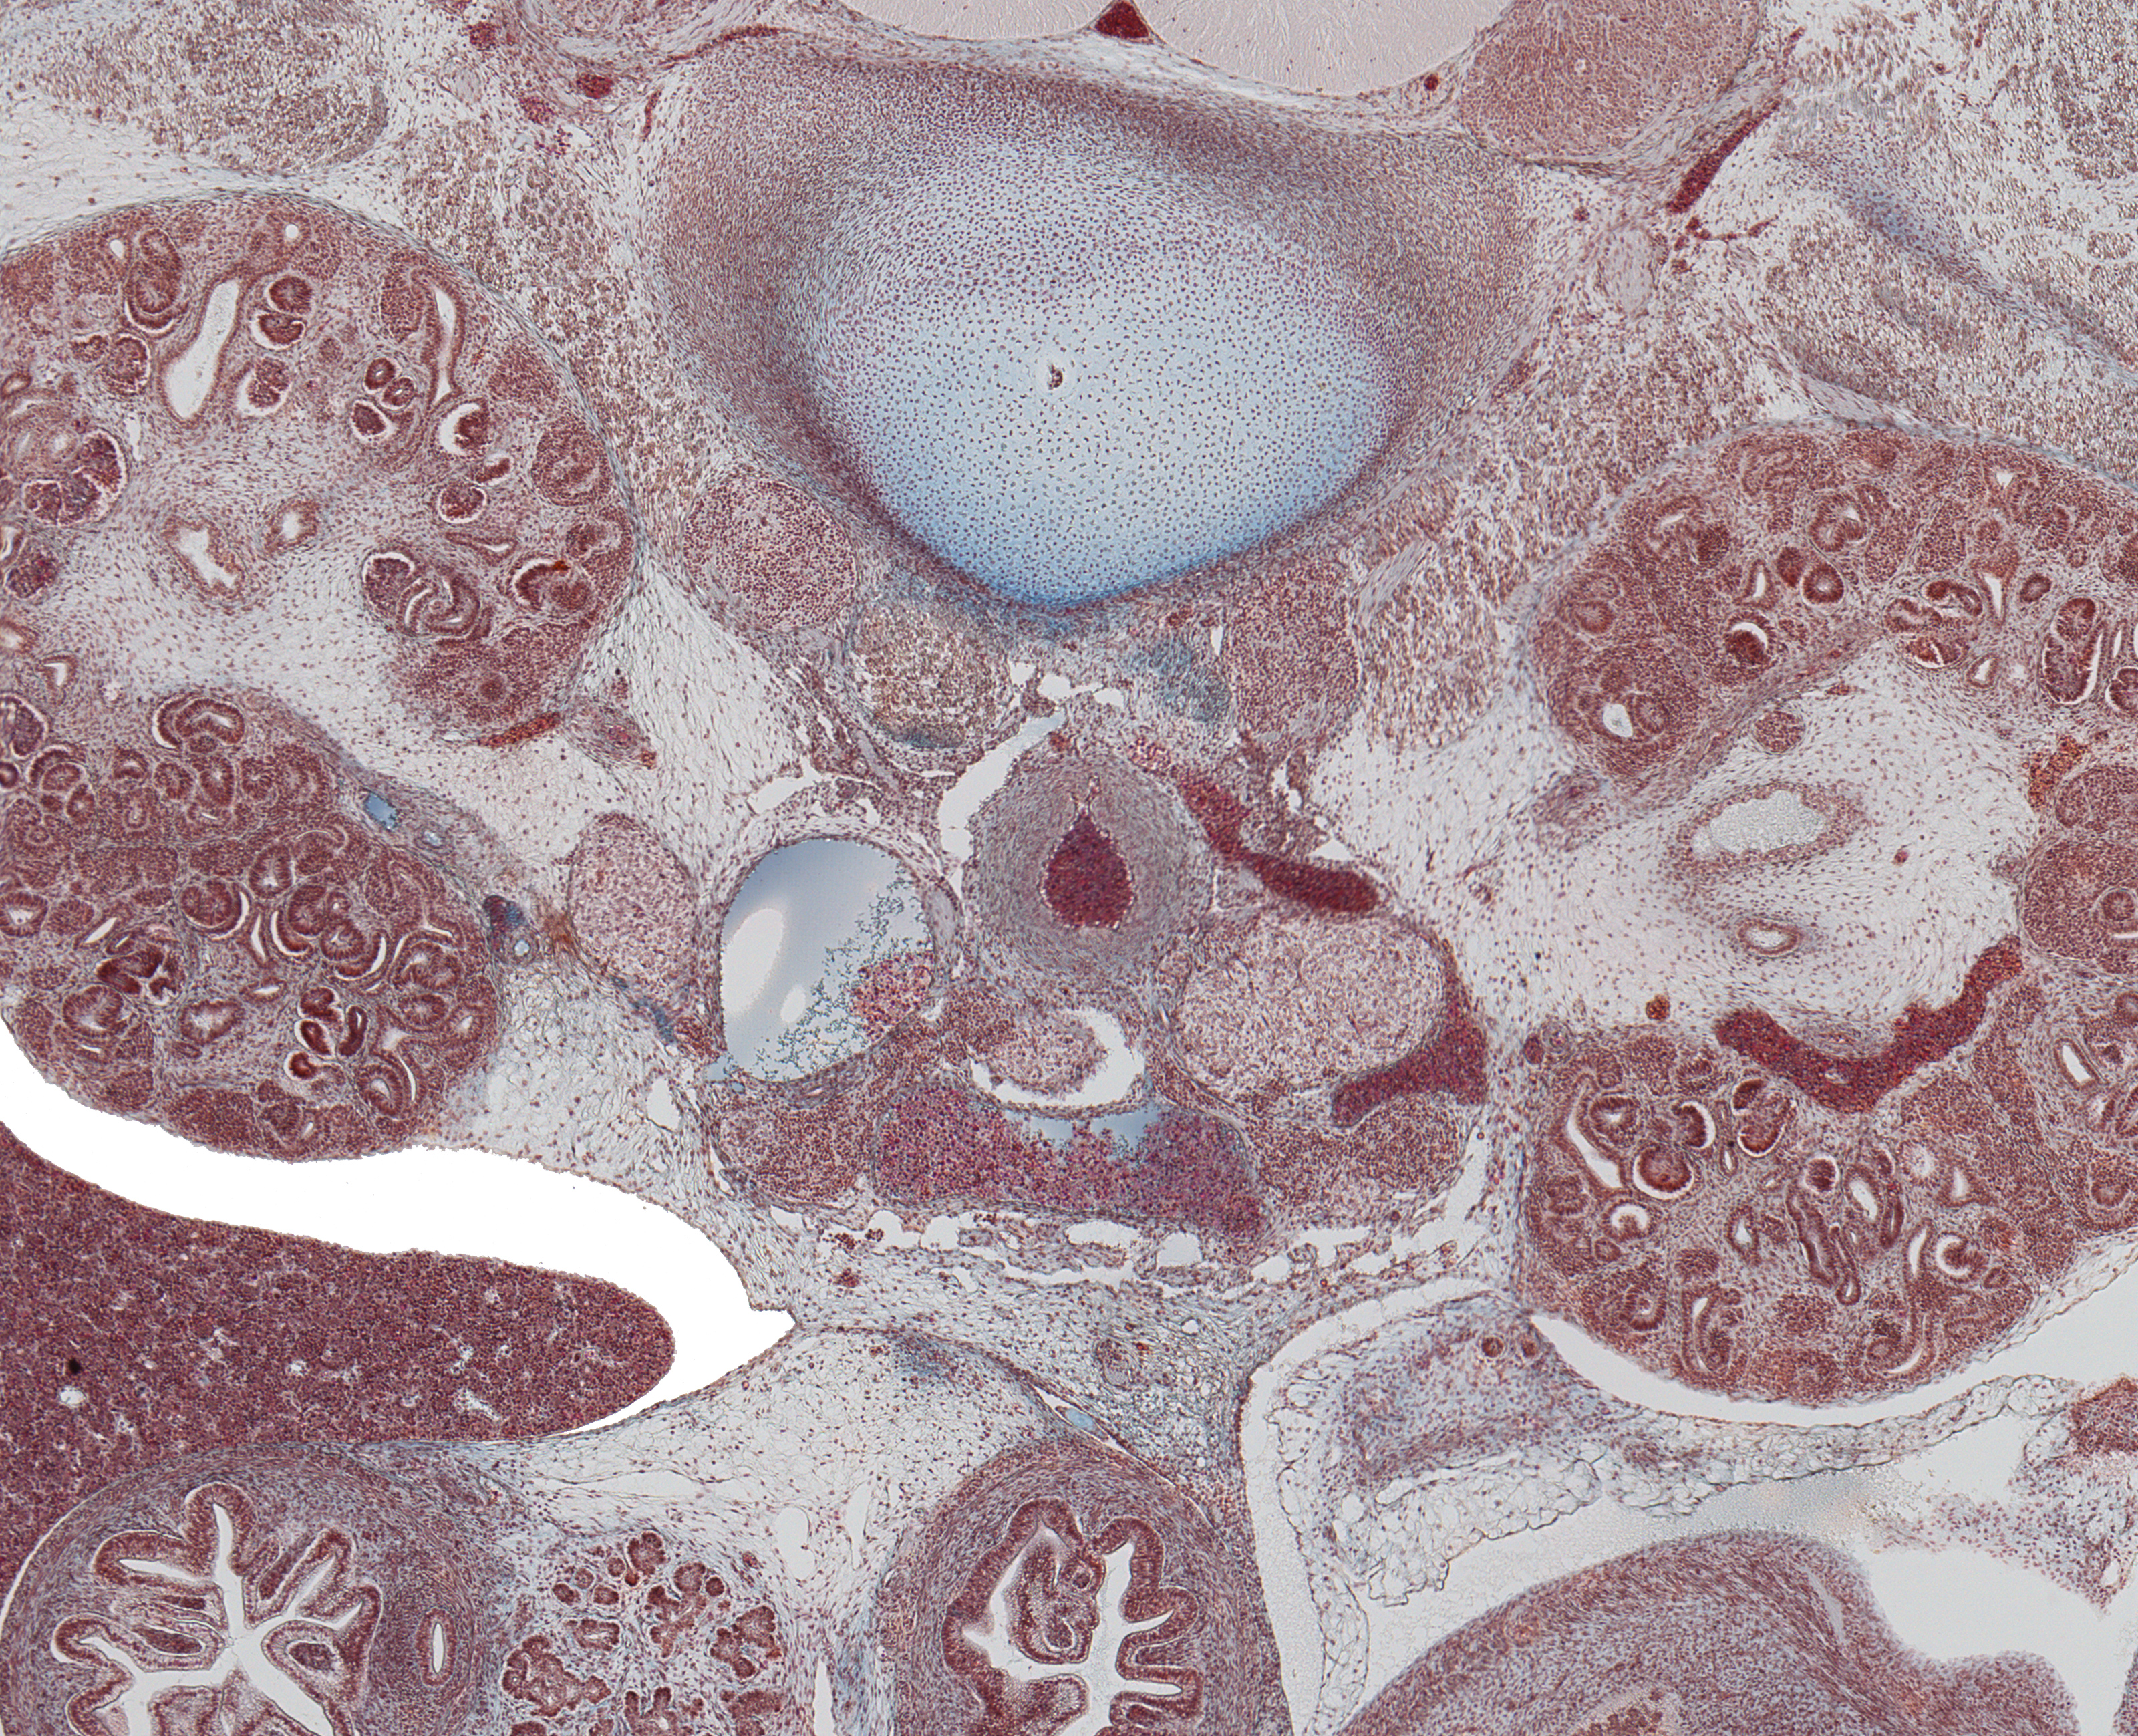

Tissue

–

Hilum of Kidneys

Carnegie Embryo #9226

Location:

175-01-01